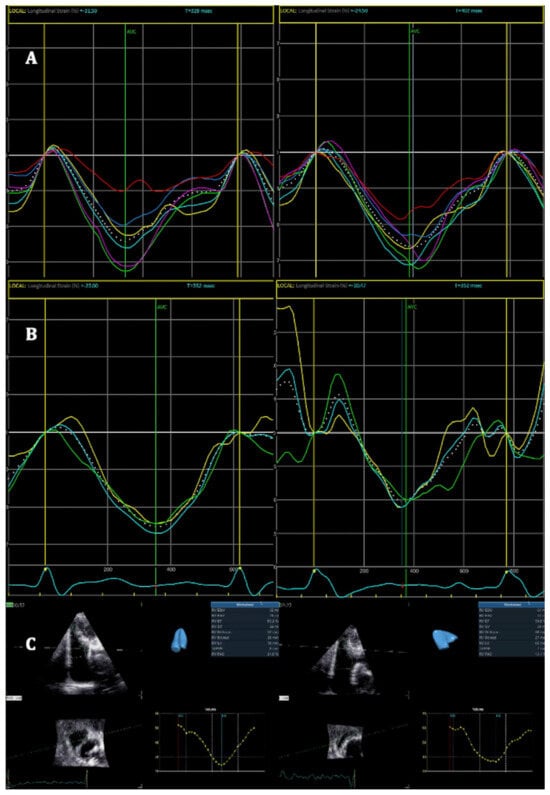

4. Results